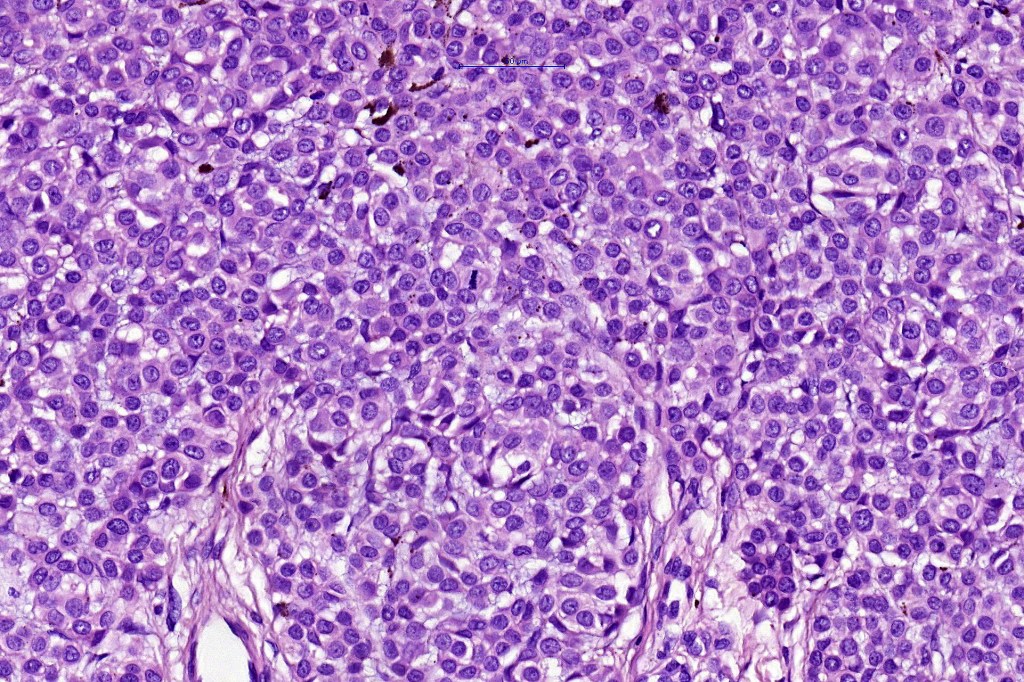

•Expansile nodules or diffuse

•Mimics type-A cells, (lesions which mimic type B nevus cells are often classified as small cell melanoma, this is important as the differential diagnosis is very different- see separate blog)

•Subtle or not so subtle impaired maturation with depth (sometimes this is evident at scanning magnification)

•Subtle nucleolar prominence

•Subtle pleomorphism

•Mitoses invariable including often in the deep aspect

•Cyclin D1 & Ki67 often show marked expression